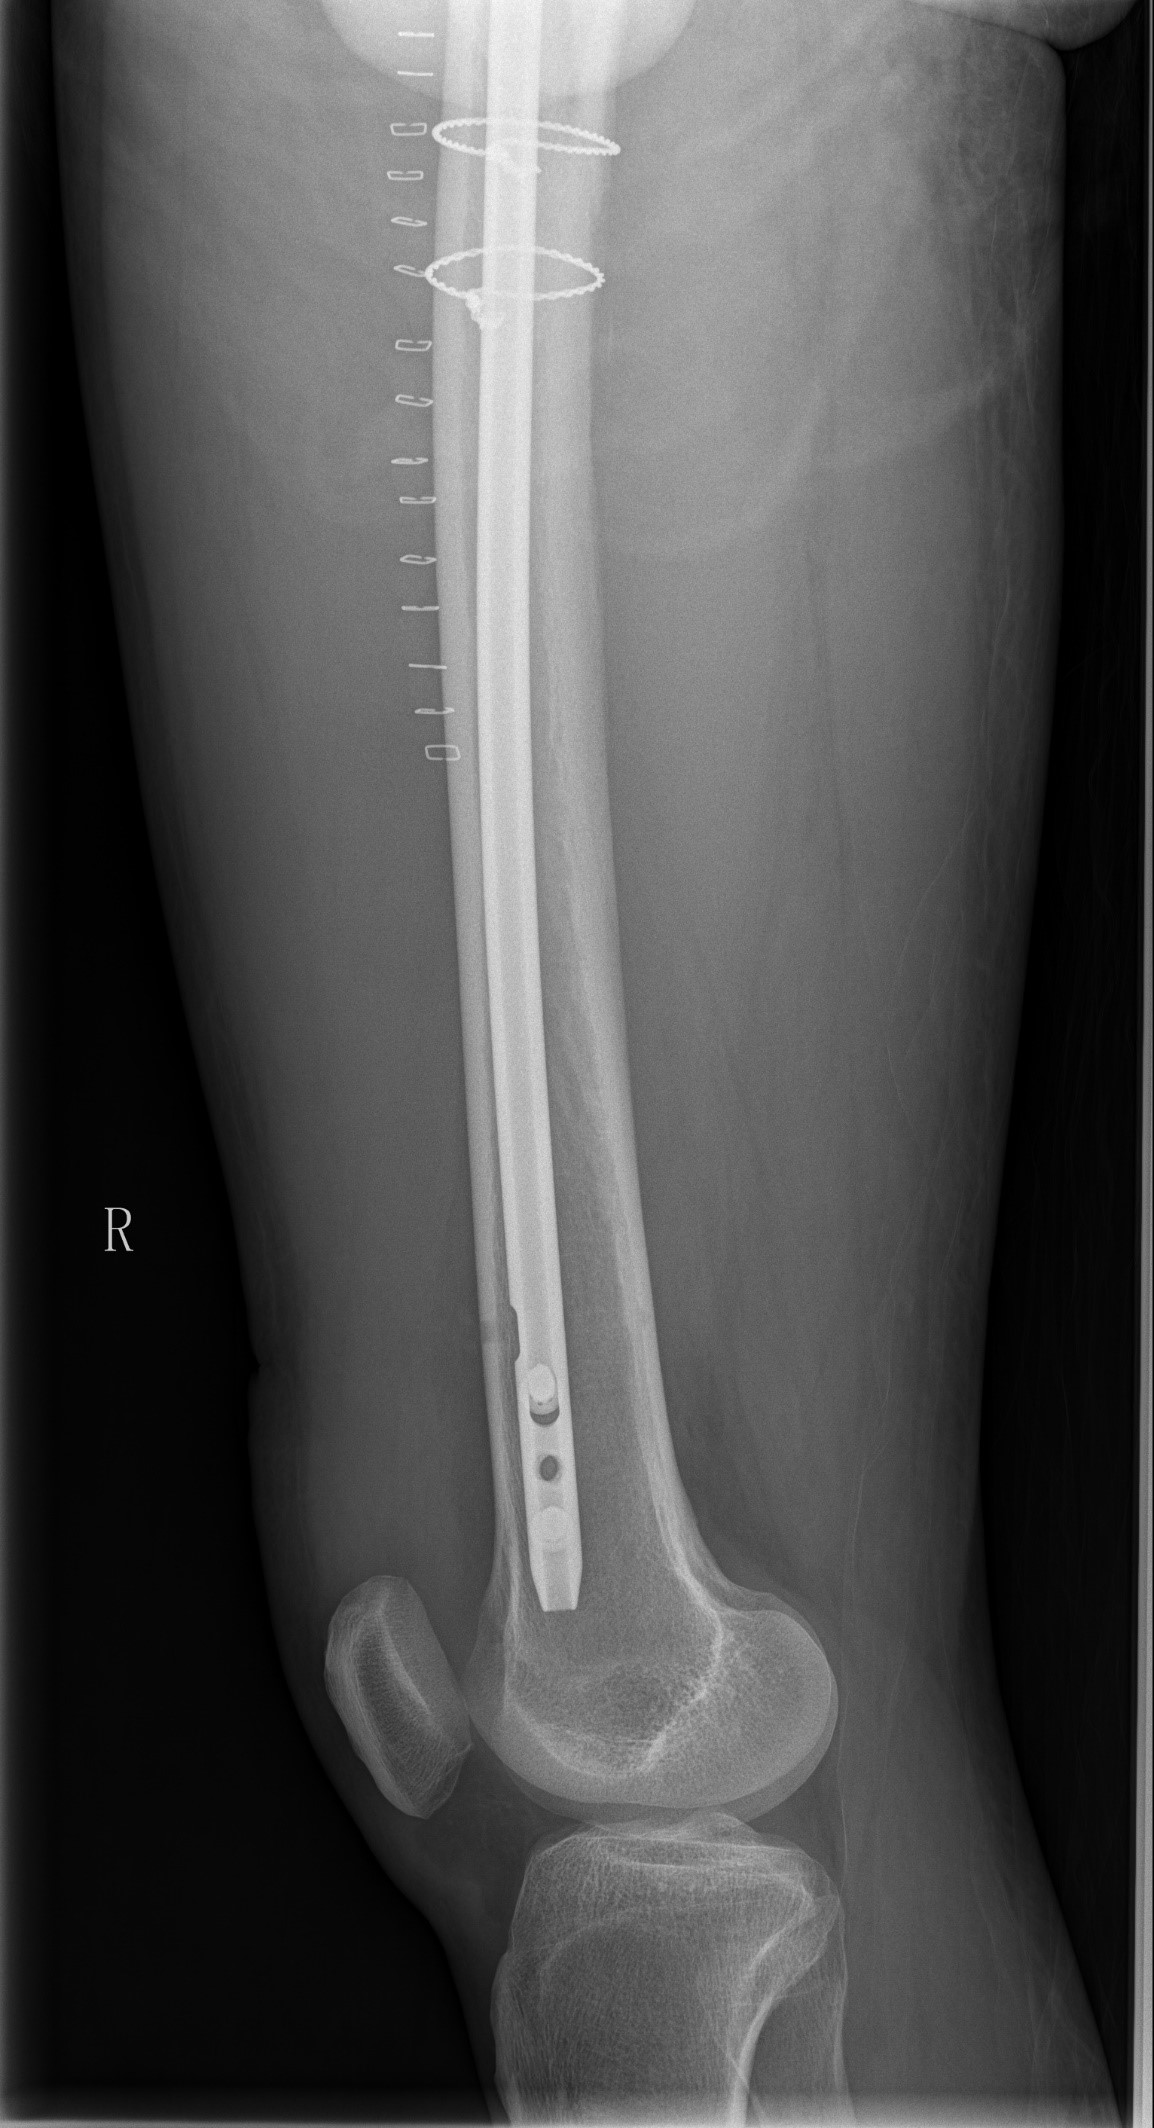

案例三:59岁女性假体周围骨折

患者情况:吴女士,5年前曾在我院接受人工髋关节置换术,近日因在家中地板湿滑处摔倒,导致假体周围骨折。

治疗难点:

1.摔伤后需评估假体是否松动;

2.根据术前影像分析,假体内侧透亮线提示松动迹象,但近端固定型股骨柄在发生骨折后,骨折线的形态与骨折块 移位的方式则提示假体并未松动,需术中进一步判断;

3.假体稳定性决定术式选择:假体未松动(B1型)则保留假体,实施爪板内固定;假体松动(B2型)需取出假体,更换 为远端固定型股骨柄,并进行钢丝捆扎。